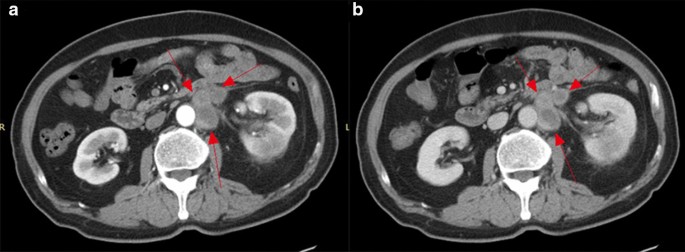

Enhancement characteristics

Compared with the adjacent normal renal parenchyma, the parenchymal area of 13 CDC tumors was characterized by isodensity or slightly higher density on unenhanced CT. The Hounsfield unit (HU) values on CT ranged from 37.00 to 41.55 HU, and the average value was 38.71 ± 1.53 HU (the average CT value of the same layer of renal cortex was 38.17 ± 2.78 HU). In eight (61.5%) cases, uneven patchy slight (seven cases, 35.8%) to moderate (1 case, 7.7%) enhancement of the solid area of the tumor was observed on enhanced CT (Fig. 4). There was no enhancement in the cystic and necrotic areas. The mean CT value was 61.61 ± 5.81 HU in the cortical phase (the average CT value of the renal parenchyma was 170.85 ± 56.48 HU). The net increase in the CT value in the cortical phase was 23.50 HU. The CT value in the medullary phase was 68.47 ± 10.64 HU (the average CT value of the renal parenchyma was 137.44 ± 34.38 HU). In the excretion period, nine tumors showed low attenuation compared with that of the normal parenchyma. The CT value in the excretion period was 65.47 ± 5.60 HU (the average CT value of the renal parenchyma was 120.25 ± 17.91 HU). The CT value increased from 10.00 to 39.04 HU with an average of 26.90 ± 8.32 HU from the unenhanced CT to the medullary phase enhanced CT (Table 2).

Local invasion and distant metastasis

In nine of thirteen (69.23%) cases, CT images showed evidence of intra-abdominal metastatic disease (Table 1). Perirenal infiltration is common in renal CDC. In this group, perirenal fat blurring or prerenal fascia thickening was observed in 12 (92.3%) cases. Direct invasion as peritoneal and lymphatic metastasis was observed in nine (69.2%) cases (Fig. 7a, b). In seven cases, the metastases surrounded the renal artery and caused renal artery stenosis (Fig. 5a, b). Adrenal gland involvement was observed in two (15.4%) cases and included the left side in one case and bilateral involvement in one case. Inferior vena cava involvement was observed in one (7.7%) case. There were three (23.1%) cases of bilateral lung metastasis, one (7.7%) case of bilateral pleural metastasis, one (7.7%) case of brain metastasis, and one (7.7%) case of bone metastasis (right ribs, right pubic symphysis, and left scapula).

The majority of CDC tumors in the present cohort were hypovascular. Most of the CDC tumors in the dynamic enhanced scan showed a relatively low density in the renal cortex and medulla. The parenchyma of the mass was uneven, showing light to moderate enhancement in the cortical or medullary phase that was lower than that of the surrounding renal parenchyma. The medullary phase showed uneven and mildly delayed enhancement. The degree of enhancement was lower than that of the renal parenchyma, which is consistent with the results of a Chinese study [20]. This enhancement pattern differed from that of blood-rich clear cell renal cell carcinoma, renal medullary carcinoma, renal angiomyolipoma, and renal angioma [21]. Seong et al. [14]. reported that unlike more common conventional RCC, contrast-enhanced CT scans of CDCs usually show weak (69%) and heterogeneous enhancement (85%). This enhancement pattern differs from that of renal clear cell carcinoma, which shows significant enhancement in the cortical phase, with the density reaching a peak and decreasing markedly during the medullary phase. This enhancement pattern of CDC tumors also contributes to the identification of renal clear cell carcinoma. Fujimoto et al. analyzed the enhancement pattern of RCCs greater than 5 cm in diameter on contrast-enhanced helical CT. They reported that strong enhancement comparable to that of the renal cortex was detected only in conventional RCC (75%) [22]. Jeong et al. reported that conventional renal carcinomas show a stronger enhancement than nonconventional renal carcinomas in both the corticomedullary and excretory phases. Tumors with > 84 HU in the corticomedullary phase and 44 HU in the excretory phase are likely to be conventional renal carcinomas, whereas the present data showed a 23.5 HU increase in the cortical phase [23].